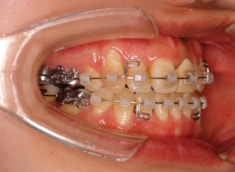

治療開始時

治療法:表の矯正(T21ブラケット)